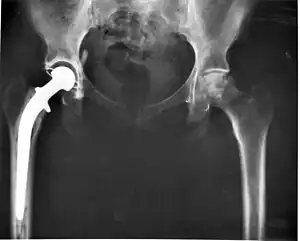

Il repose sur la radiographie de la hanche :

- arthroplastie de hanche ou « prothèse totale de hanche » qui consiste à remplacer l'extrémité supérieure du fémur par une prothèse métallique et à insérer au niveau du cotyle (partie de l'articulation située sur l'os du bassin), une cupule scellée ou vissée. L'articulation entre les deux pièces fait appel à des dérivés plastiques ou à de la céramique.